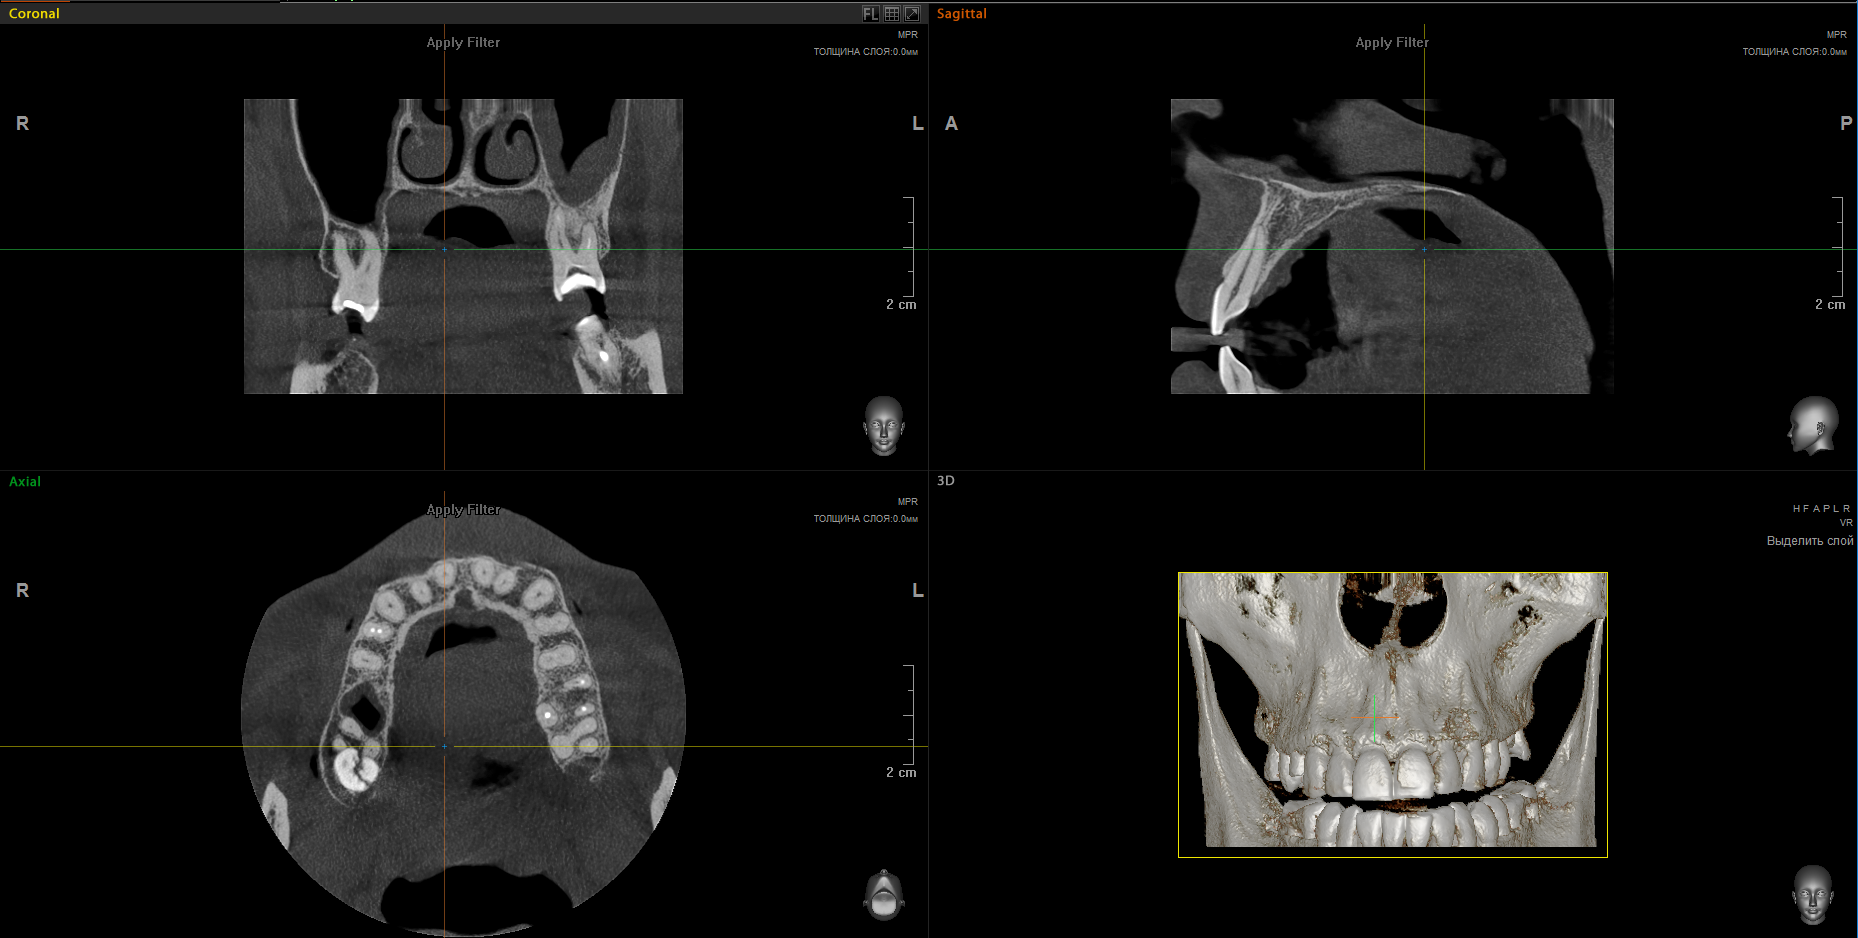

Computed tomography of one jaw

Computed tomography of the jaws